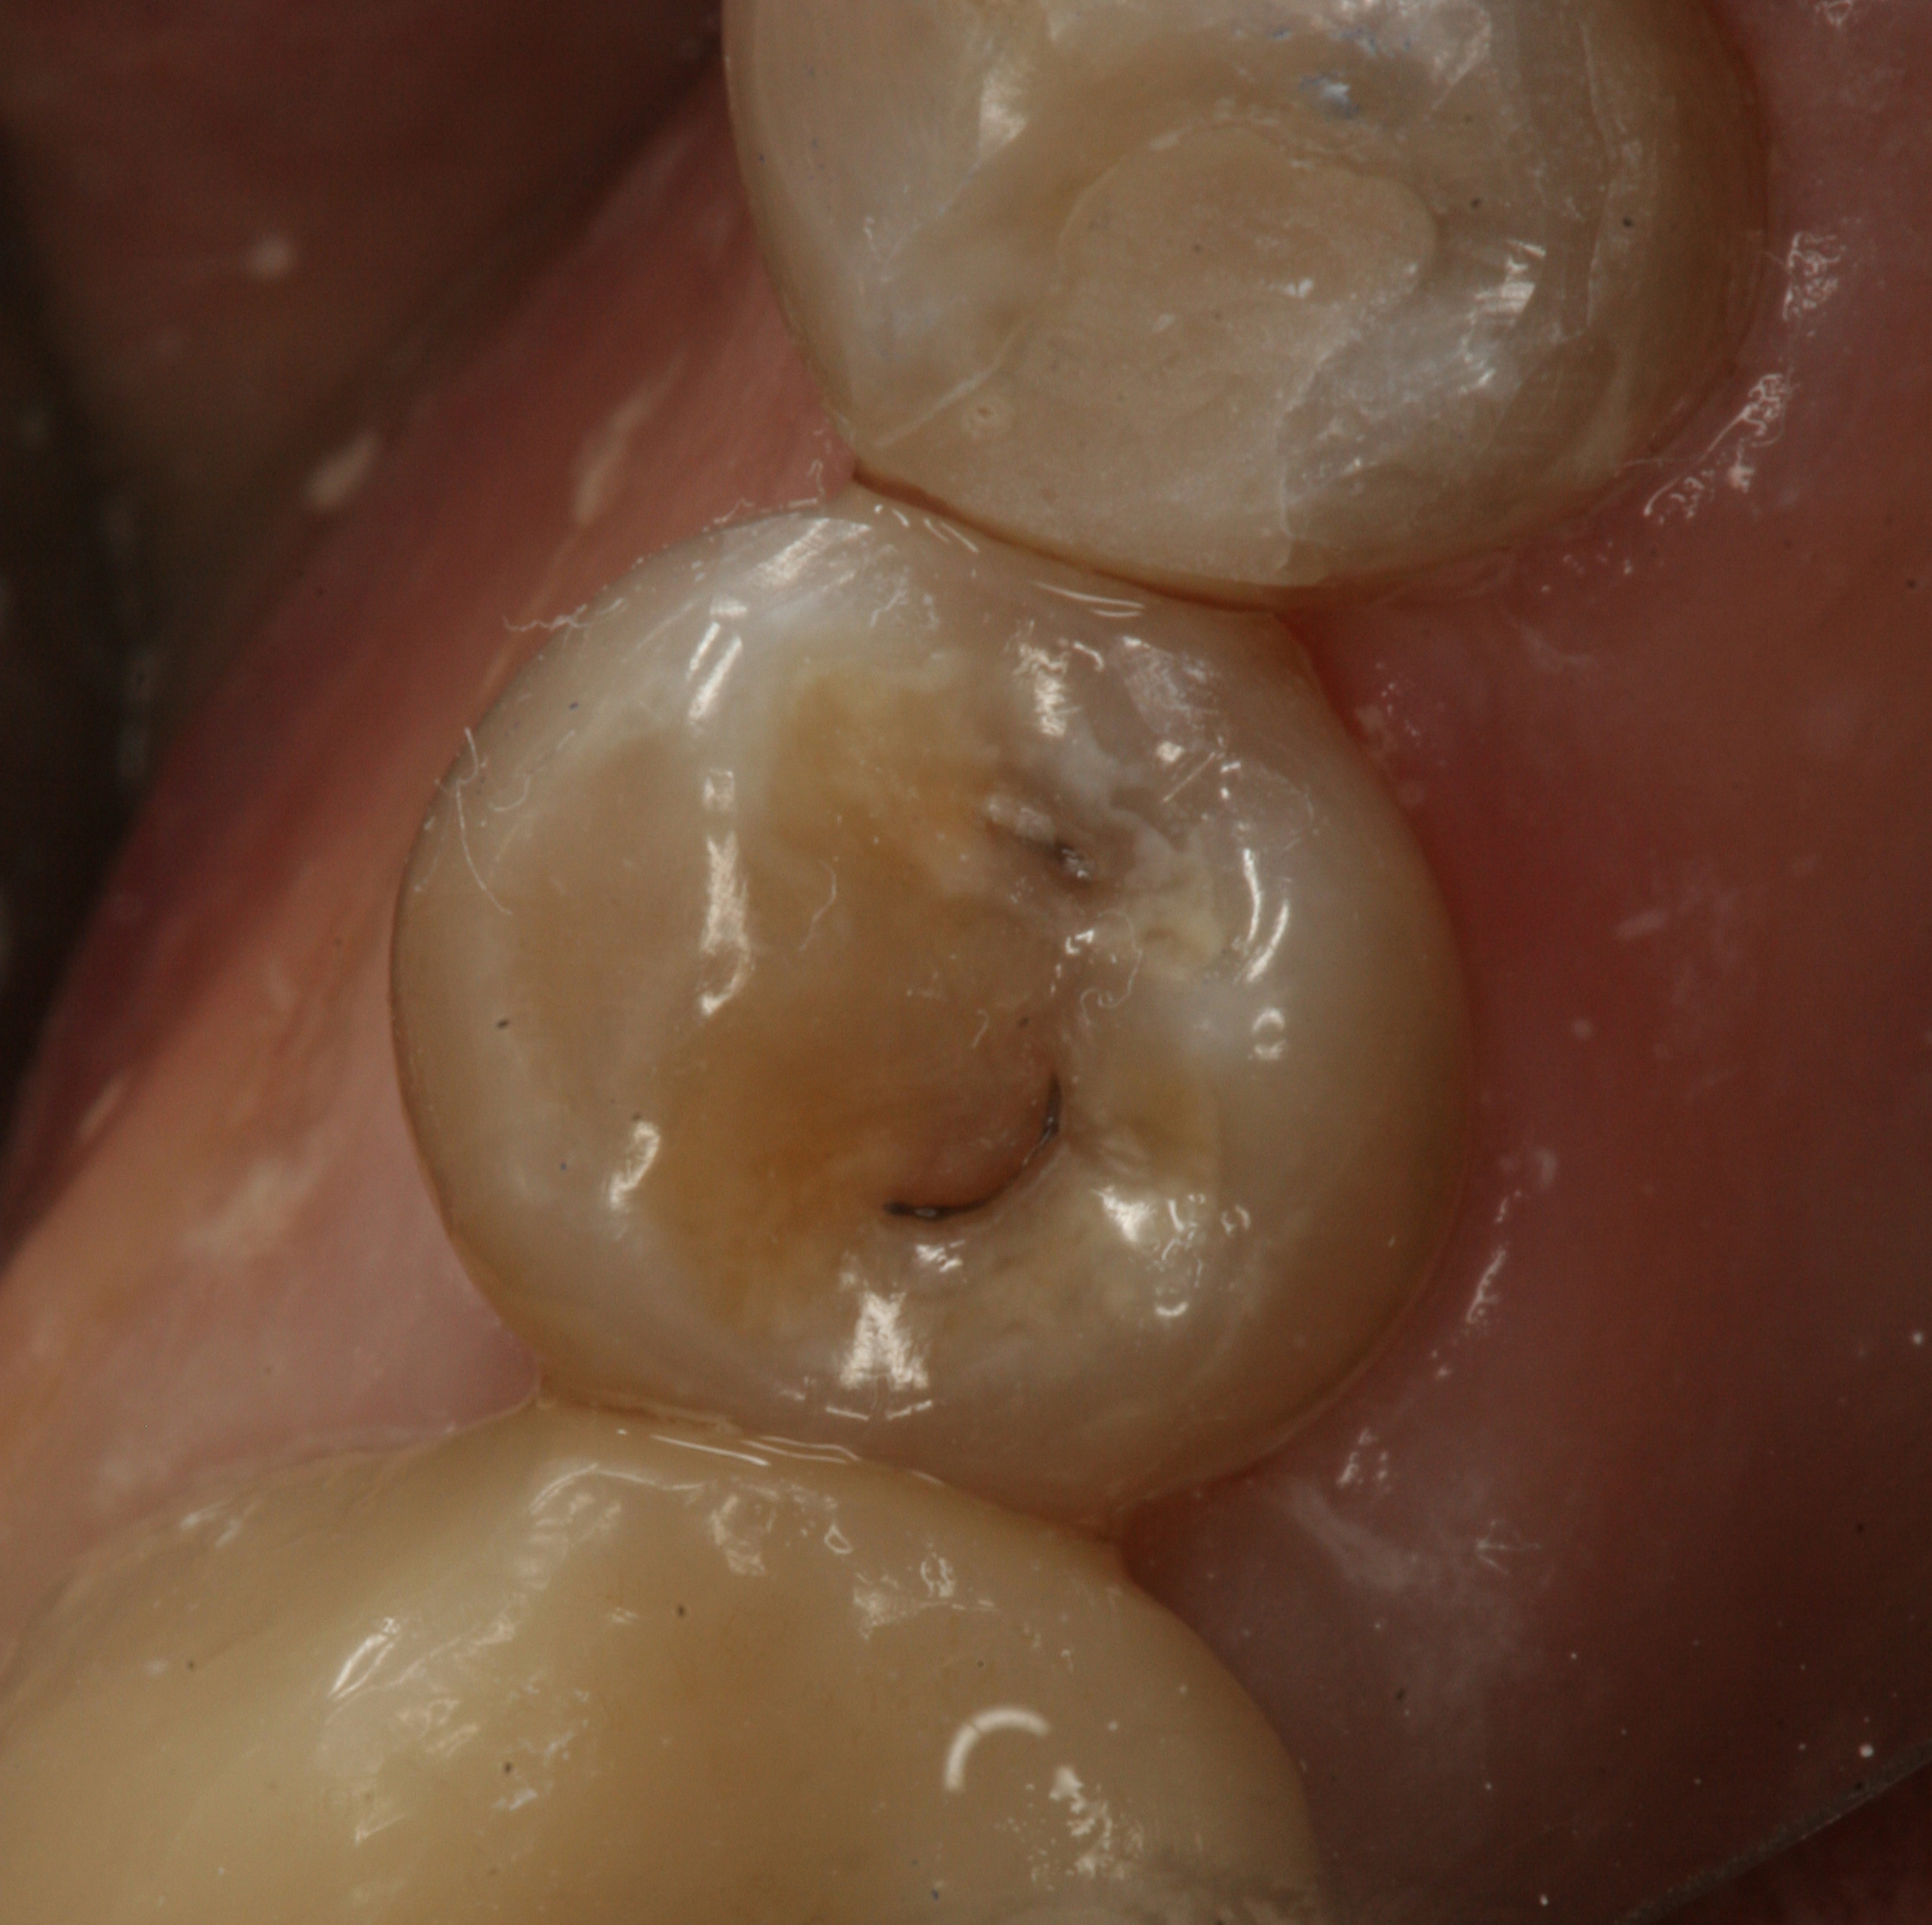

Fig 4. Preoperative view of a maxillary left central incisor after a traumatic incident that had caused loss of the mesial and incisal portion of the tooth.

Figure 4

Fig 5. Postoperative view of the restored tooth using a smart-matching resin composite without using a mirror-backing technique. Note the lower value of the incisal edge.

Figure 5